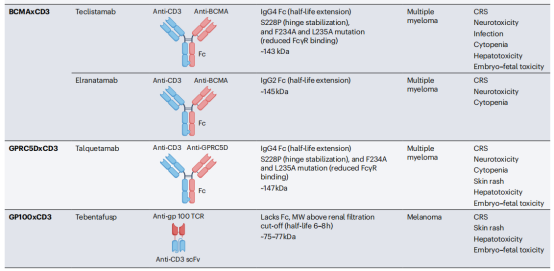

双特异性抗体可以结合两种不同的抗原或表位,抗原既可以定位在同一靶细胞上,也可定位在不同靶细胞上,针对两种不同细胞的双特异性抗体大多是T细胞连接物,将癌细胞与效应细胞交联,称为T细胞接合器(TCE)双特异性抗体。交联后,效应T细胞被激活,通过释放细胞毒性颗粒和淋巴因子来杀死结合的靶癌细胞。另一类双特异性抗体参与由同一靶细胞表达的不同抗原,例如两种不同的生长因子受体。这种双特异性抗体通过阻断通过目标生长因子受体的增殖信号,以及激活NK细胞和巨噬细胞来杀死癌细胞,从而杀死目标细胞。

常见的TCE双特异性抗体格式包括BiTE,Genmab,DART,Xmab,其中Blinatumomab使用BiTE格式。Glofitamab是一种用于淋巴瘤的的CD20xCD3双特异性抗体,并且具有独特的2:1的T细胞参与双特异性格式,它与传统的1:1靶细胞与CD3结合设计相比,这种格式具有更高的肿瘤杀伤作用。一般全长治疗性抗体使用的格式是IgG型,IgG有两个抗原结合位点,IgM是一个五聚体,它有10个抗原结合位点,与针对相同表位的IgG抗体相比,这提供了更高的结合亲和力。Imvotamab是一种CD20xCD3 IgM双特异性抗体,已在晚期B细胞恶性肿瘤患者中显示出完全缓解。

双特异性抗体也被设计用于结合目标癌细胞上的两种不同抗原或表位,而不涉及效应T细胞。它们的抗癌作用是通过阻断两种增殖信号通路介导的,从而最大限度地发挥抗肿瘤活性。除了它们的受体阻断活性外,这些双特异性抗体也可以被设计成含有一个功能性的IgG1Fc结构域,使它们能够通过非T细胞免疫效应途径(如ADCC、ADCP和CDC)杀死癌细胞。Amivantamab是第一个靶向癌细胞表达的EGFR和MET的受体阻断双特异性抗体被批注用于治疗非小细胞肺癌,Amivantamab的IgG1Fc结构域被设计成低聚焦水平,从而增强FcγRIIIa结合和NK细胞介导的ADCC。TCE双特异性抗体会引起细胞因子释放综合征(CRS)和神经毒性,受体阻断双特异性抗体不能激活T细胞,一般不会诱导CRS和神经毒素。